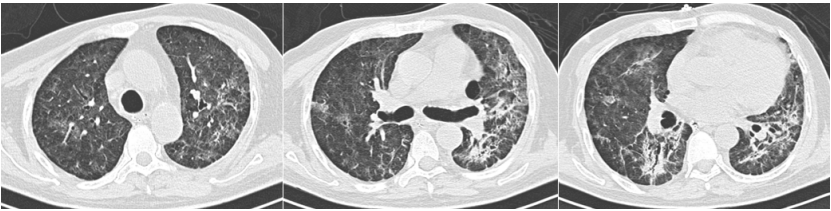

2023年1月12日,患者无明显诱因出现咳嗽,呈阵发性刺激性咳嗽,咳少量白痰。伴活动后气短,无发热、鼻塞、流涕、胸痛、咯血。自行口服止咳药物(具体不详)治疗,症状无明显缓解。2023年1月19日于当地医院住院治疗。查新冠核酸阳性。肺部CT示:沿支气管血管束分布的磨玻璃影,中心向四周扩散,考虑双肺感染;冠状动脉钙化;肝囊性灶;胆囊壁水肿(图1)。给予抗感染、输注丙球、新冠恢复期血浆等治疗。1月23日复查肺部CT示实变增多,右下肺有支气管充气征(图2)

图片

图1  患者肺部CT(2023-01-19)

图2  复查肺部CT(2023-01-23)

治疗2天后带患者外出做头胸部CT:考虑左侧枕叶脑出血(图5),建议短期复查除外其他;双肺磨玻璃影伴斑片影,考虑多发感染(图6)

图6  胸部CT(2023-02-03)